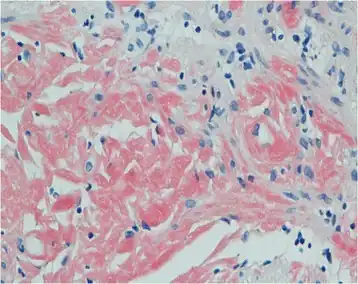

Primary systemic amyloidosis initially presenting with digestive symptoms-gastric mucosa showed orange-red positivity

Both blood and the urine can be tested for the light chains, which may form amyloid deposits, causing disease. However, the diagnosis requires a sample of an affected organ.[5][8] Other diagnosis can be tissue biopsy. Tissue biopsy tests a tissue sample to look for amyloid deposits. The tissue is stained with red dye, and under a microscopic examination, amyloid proteins can be detected if the tissue turns an apple-green color. [9]